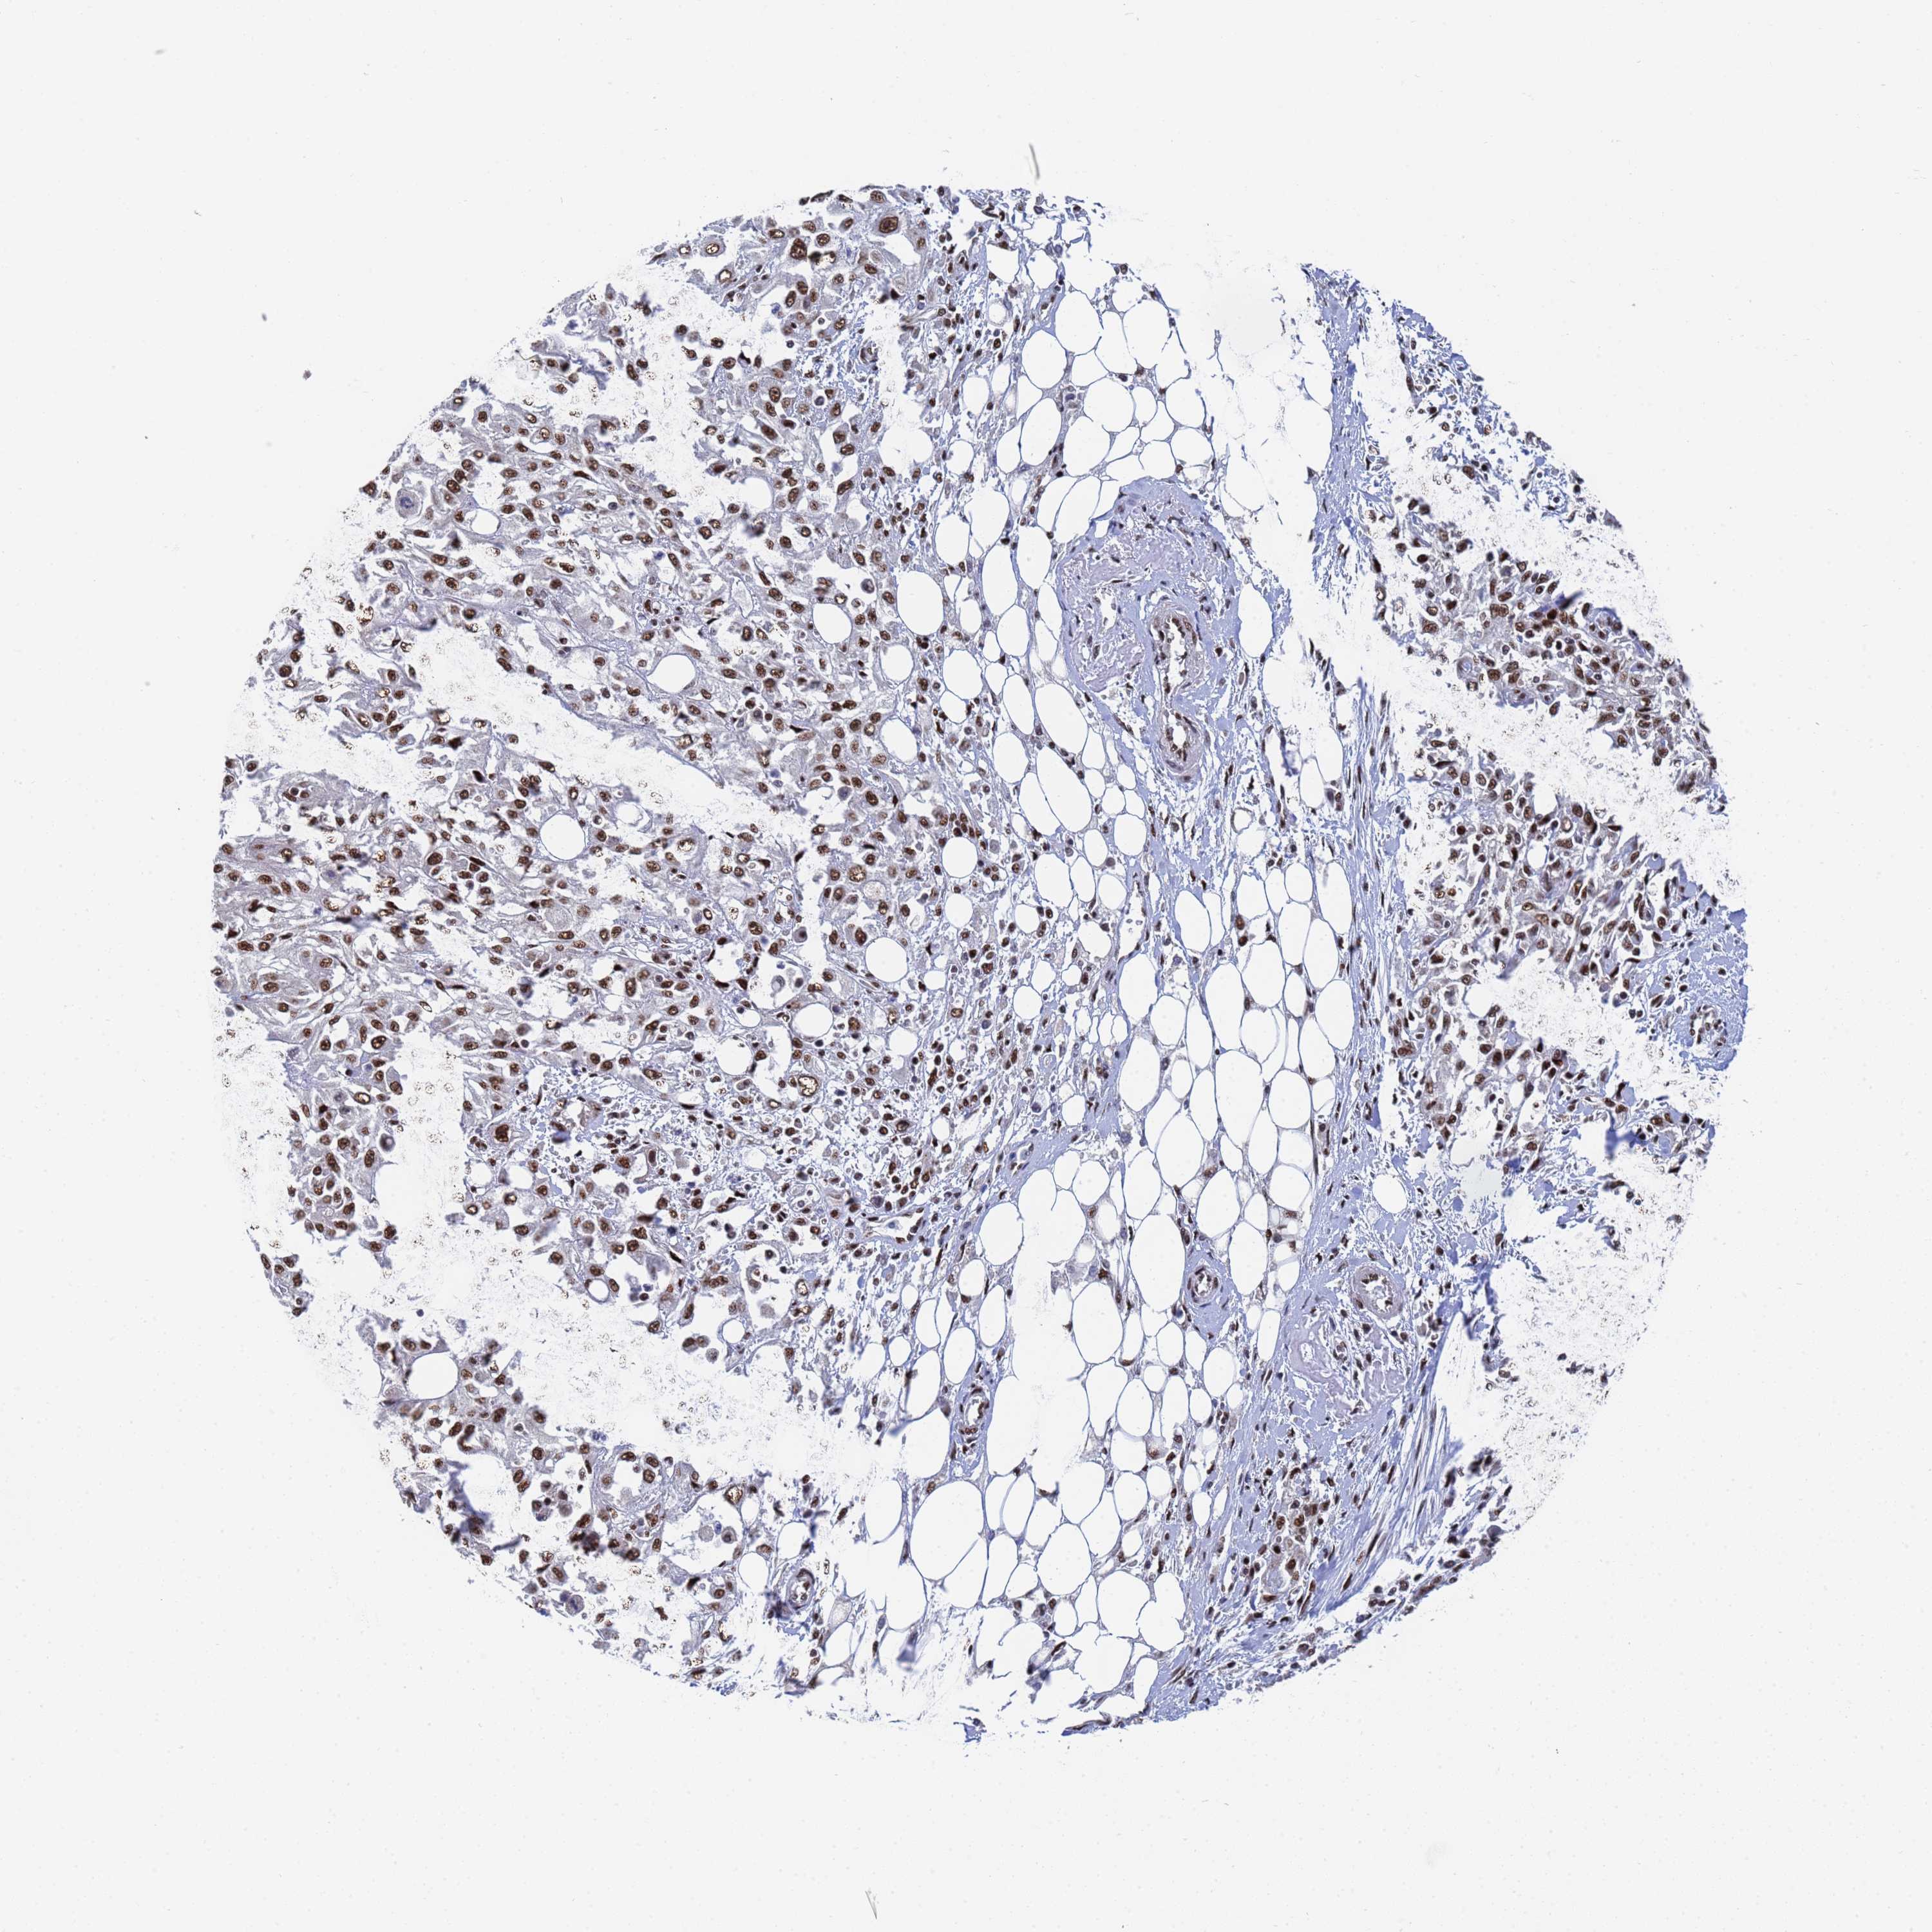

Basal cell and squamous cell cancer

SKIN CANCER - Protein expressioni

A mouse-over function shows sample information and annotation data. Click on an image to view it in a full screen mode. Samples can be filtered based on level of antibody staining by selecting one or several of the following categories: high, medium, low and not detected. The assay and annotation is described here.

Antibody stainingi

Antibody staining in the annotated cell types in the current human tissue is reported as not detected, low, medium, or high, based on conventional immunohistochemistry profiling in selected tissues. This score is based on the combination of the staining intensity and fraction of stained cells.

Each image is clickable and will lead to virtual microscopy that enables deeper exploration of all samples and also displays staining intensity scores, fraction scores and subcellular localization as well as patient and tissue information for each sample.

Antibody HPA035693

Staining

High

Medium

Low

Not detected

Intensity

Strong

Moderate

Weak

Negative

Quantity

>75%

75%-25%

<25%

None

Location

Nuclear

Cytoplasmic/membranous

Cytoplasmic/membranous,nuclear

Basal cell carcinoma